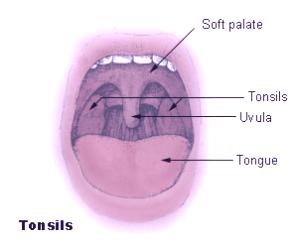

Tonsils are two clumps of lymphoid tissues located at the sides of the throat. The tonsils help in fighting off various infections. When the tonsils encounter bacteria or other harmful foreign bodies, they secrete mucous that helps destroy the bacteria or viruses that enter the body through the mouth. The excessive mucous secreted by the tonsils form into pus on tonsils. This pus can be painful and annoying but the presence of pus doesn’t indicate any disease but merely a symptom of tonsil infection or inflammation.